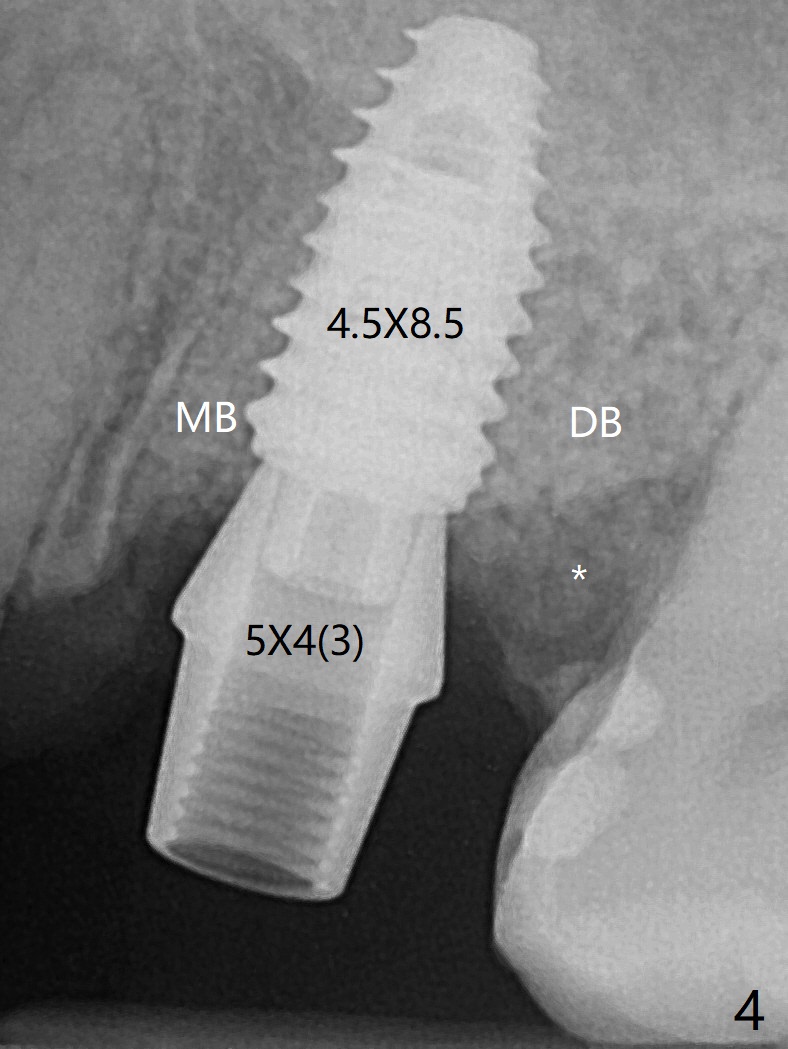

虽然没有保留左上6牙根,但是导板好像帮助钻洞(O)正好位于中隔当中(图一,二)。使用4.5(不是4.0)x10毫米钻头后,粘性骨粉和报废植体完成上颌窦提升术(图三:S)。拔除第一磨牙后发现第二磨牙近中面龋齿,立刻进行保守修补(图三:箭头);两个磨牙之间还有骨质吸收(*)。放置正式植体(10Ncm)后(图四),三个牙槽窝填入骨粉,包括近中颊侧(MB)和远中颊侧(DB),这时磨牙间缺损初步填补(*),然后放置基台以及基台周围骨粉,进一步充填磨牙间缺失(图五:*)。术后临时牙冠脱落两次,病人自己放回去,术后一周取出牙冠,骨粉还在(图六),腭侧有单纯疱疹病变(图七:>),开抗病毒漱口水处方,然后使用临时粘固粉。术后7个月15号牙近中牙槽嵴增高大约1.4毫米(图八:空箭头,从近中最颈部树脂算起)。术后七个月临时牙冠一直使用,防止食物坎塞,有利于骨质再生。术后7个月基台在口内没有更动(术中手拧紧),牙冠口内粘固,少量粘固剂遗留(图八:^)。牙冠/基台取出,去除粘固剂,牙冠/基台就位,用扳手拧紧(30 Ncm),基台与植体仍保持完全接触(图九)。只要植体植入角度好,没有倒凹,牙冠/基台再次就位就没有问题。